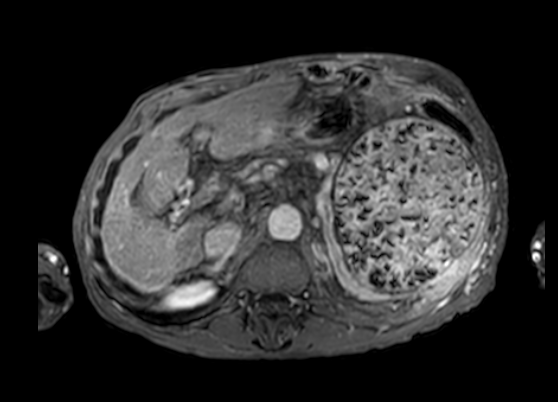

Nome do procedimento: EMBOLIZAÇÃO DE ARTÉRIA ESPLÊNICA

-COMORBIDADES: HAS; DISTÚRBIO VENTILATÓRIO OBSTRUTIVO LEVE COM CAPACIDADE VITAL REDUZIDA; CÂNCER DE PELE; HÉRNIA INGUINAL À ESQUERDA; HIPERTENSÃO PORTAL E VARIZES ESOFÁGICAS ASSOCIADA A ESQUISTOSSOMOSE HEPATOESPLÊNICA; CATARATA

Exames séricos e de imagem:

HEMOGRAMA: Eritrocitos 3,49 Milhoes/mm³, Hemoglobina 12,6 g/dL, Hematocrito 38,3%, VCM 109,7 fL, Plaquetas 43000 /mm³ (Diminuidas em lamina)

Galeria de imagens: 4421,4422